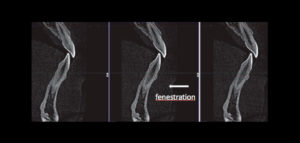

Se sabe que la tomografía computarizada de haz cónico (CBCT) produce exploraciones tridimensionales de la dentición, las estructuras duras maxilofaciales y la relación de las